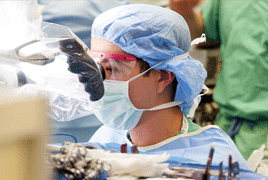

- Výsledky reoperací perzistující primární makulární díry

- Postradiačná makulopatia u pacientov s malígnym melanómom corpus ciliare a chorioidey po stereotaktickej rádiochirurgii